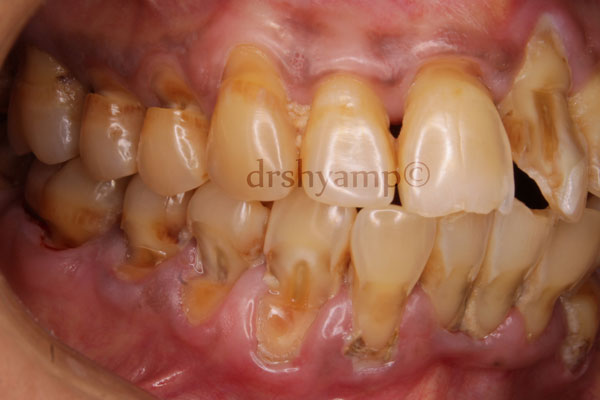

Abfraction can be defined as the loss of tooth structure from flexural forces. The teeth have a tendency to flex under pressure and this causes tension on one side of the tooth and compression on the other side of the tooth thereby causing V and C shaped impressions on the sides under tension and compression respectively. This theory is controversial and is yet to be fully proven in research.

Abrasion refers to the loss of tooth substance induced by mechanical wear other than that of mastication. Abrasion results in saucer-shaped or wedge-shaped indentations with a smooth, shiny surface. Improper toothbrushing with an abrasive dentifrice and the action of clasps are common causes of abrasio.n

erosion is a sharply defined, wedge-shaped depression in the cervical area of the facial tooth surface. Erosion generally affects a group of teeth. Suggested causes include decalcification by acidic beverages or citrus fruits and the combined effect of acid salivary secretion and friction

Treatment can include simple fillings , desensitising pastes, use of night guards and in more severe case root canal traetment and crowns. Your Dentist will be in a better position to explain the treatment modality based on clinical and radiographic examination